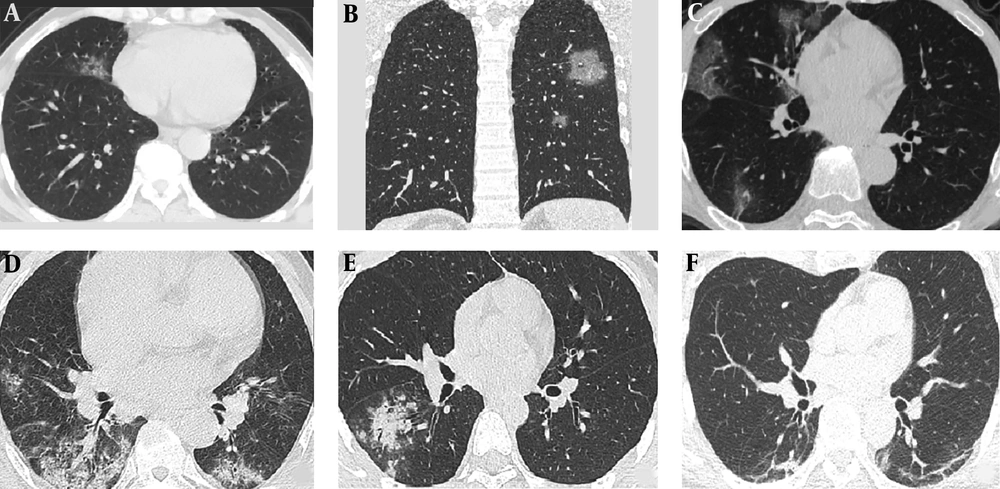

There was an overall agreement regarding main CT pattern classification for intra-observer (K = 0.931, P < 0.001), and inter-observer readings (K = 0.912, P < 0.001). According to the time between symptom onset and initial CT (1 - 11d), three stages of lung CT were assigned: stage-1: 1 - 3d, stage-2: 4 - 7d, and stage-3: 8 - 11d. The imaging findings of each stage of the disease are summarized in Table 2 and Figure 1. At stage-1 (1 - 3 days) the main CT imaging manifestations were (A) single GGO and (B) multiple GGO (Figure 2). When the course of disease progresses 4 - 7 days (Figure 3), the main imaging features were crazy paving GGO mixed with partial consolidation pattern (E). Other imaging features included multiple GGO pattern (B), nodule pattern (C), crazy paving GGO pattern (D) and consolidation pattern (F). When the disease reached 8 - 11 days (Figure 3), the main CT imaging features were consolidation pattern (F), and pattern (E). Two patients underwent CT examination on the first and fourth days of symptom onset, respectively; however, no imaging findings were observed. The total segments of lung involvement in each stage were summarized as 3 (range from 1 to 5), 5 (range from 3 to 7, P < 0.001, compared to that of stage-1), and 6 (range from 3 to 8, P < 0.001, compared to that of stage-1) in each stage.

According to the analysis, a correlation was established between the characteristics of CT patterns and the time of symptom onset. Within 3 days after onset, the majority of the lesions were characterized by single or multiple GGO. These lesions were scattered, light-density, not fused with each other, and easily missed during diagnosis. The lesions progressed rapidly in 4 - 7 days, indicating fusion into large-scale consolidation with light density or GGO separated by honeycomb-like or grid-like thickened interlobular septa. The degree of fibrosis was further aggravated between 8 and 11 days, which showed that the volume of the consolidation may reduce with the air-bronchogram inside.

The imaging manifestations of 4 - 7 days were diverse, altering rapidly, and hence, could be manifested as scattered focal GGO or a fused and large-scale light consolidation with air-bronchogram inside (B-F). These phenomena could be attributed to the following: (1) The age difference of the patients: lesions in younger patients (< 30 years) were milder, while lesions in the elderly were severe; (2) Time of treatment: If the patient visited a doctor at an early stage (1 - 3 d), the lesions were mild. If the patient visited a doctor at a later stage (> 4 d), the lesions were severe.